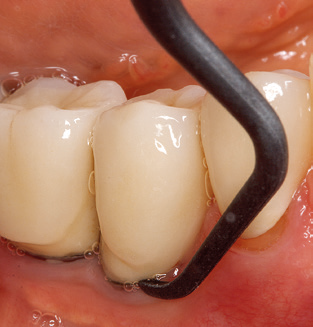

Of course, the use of instruments for mechanical removal of the biofilm is a central component of SPT and thus of primary significance. Consequently, the SPT workflow comprises both supragingival and subgingival cleaning. In our concept, a combination of hand instruments and machine cleaning has proven advantageous. A number of options are available for the mechanical procedures: sonic devices, ultrasonic devices and powder jet devices.

Although the fundamental principle of the ultrasonic devices remains, recent years have seen a whole host of further developments, resulting in an increase in efficiency, patient comfort and safety. These innovations are all present in the ultrasonic device (Tigon+, W&H Dentalwerk Bürmoos GmbH) currently employed by the authors, for example.

Good illumination of the working field facilitates the process considerably. The system used by the authors achieves this thanks to a 5x LED ring integrated in the handpiece. Naturally, a range of working tips for different indications is also offered. A straight, universally employable tip is the basic instrument required for machine cleaning of natural teeth (Fig. 5a and b). Curved tips, which allow access to exposed furcations, are also available for hard-to-reach areas in the posterior region (Fig. 6).

Of course, working tips for the cleaning of implant surfaces are also indispensable for SPT in patients fitted with implants. The implant cleaning attachment on the system used here is characterised by its tapered, hexagonal design. This design allows light, atraumatic penetration of the peri-implant pocket and displays a good cleaning performance (Fig. 7).

Fig. 4: Flexible probes with millimetre markings are recommended for the probing of dental implants (e.g. Colorvue Kit PCV11KIT6, Hu­Friedy). – Fig. 5a and b: A straight working tip (1P, W&H Dentalwerk Bürmoos GmbH) is a suitable instrument for use on all natural teeth. – Fig. 6: Curved working tips (3Pr/3Pl, W&H Dentalwerk Bürmoos GmbH) lend themselves to the processing of difficult-to-reach areas of the tooth and root surfaces (e.g. furcations). – Fig. 7: The tapered, hexagonal implant cleaning tip (1I, W&H Dentalwerk Bürmoos GmbH) permits atraumatic and efficient cleaning of the crown and abutment surfaces. – Fig. 8: Titanium and carbon curettes are suitable instruments for the manual cleaning of the implant surfaces.